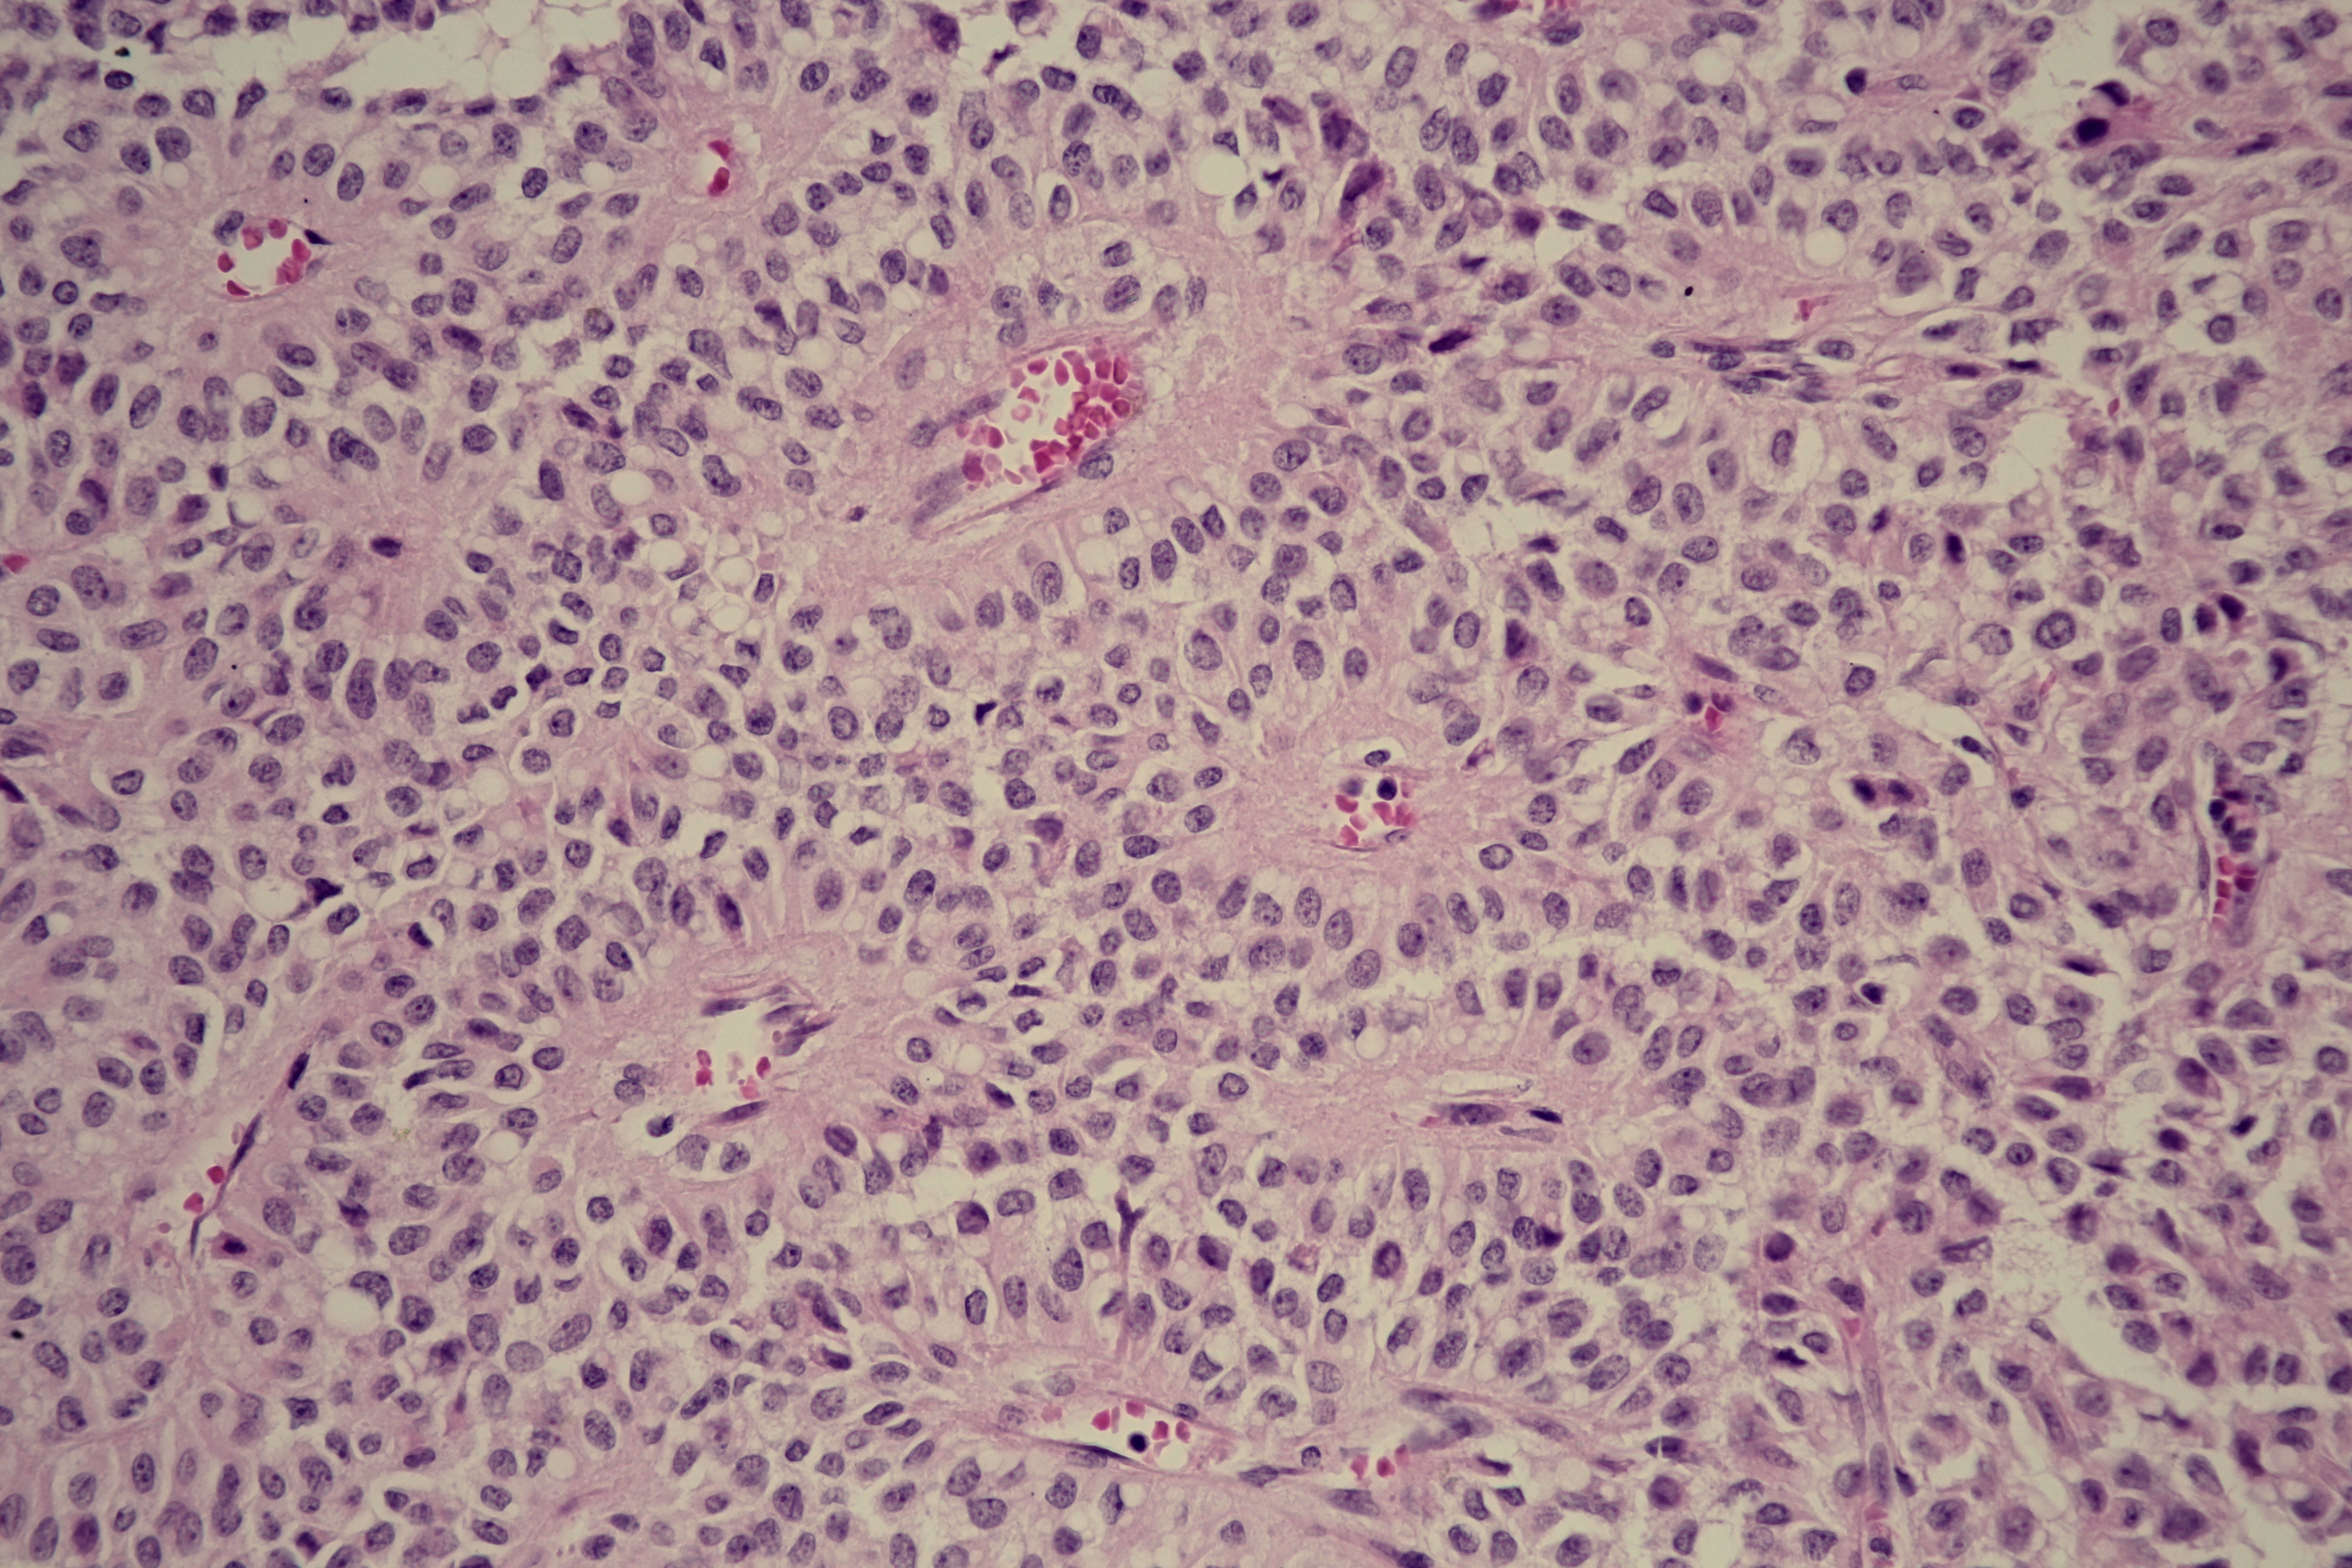

Results. Thirteen patients with SPT were identified (10 females), with a median age of 30 years. The main clinical presentation was abdominal pain (92.3%). The tumor was mostly located in the body or tail of the pancreas (77%), and the mean size was 8.2 cm. Regarding the surgical approach there were 5 distal pancreatectomies with splenectomy, 3 body and tail pancreatectomies, 2 body and tail pancreatectomies with splenectomy, 2 pancreato-duodenectomy, 1 partial enucleation and of all only 2 partial resections. Postoperative hematoxylin- eosin staining and immunohistochemistry confirmed the diagnosis in all cases. None of the patients had lymph nodes metastases. Only one local invasion. There was one case of death due to postoperative complications. Four cases followed adjuvant systemic chemotherapy. The mean follow-up was 18 months, without evidence of recurrence during this period.